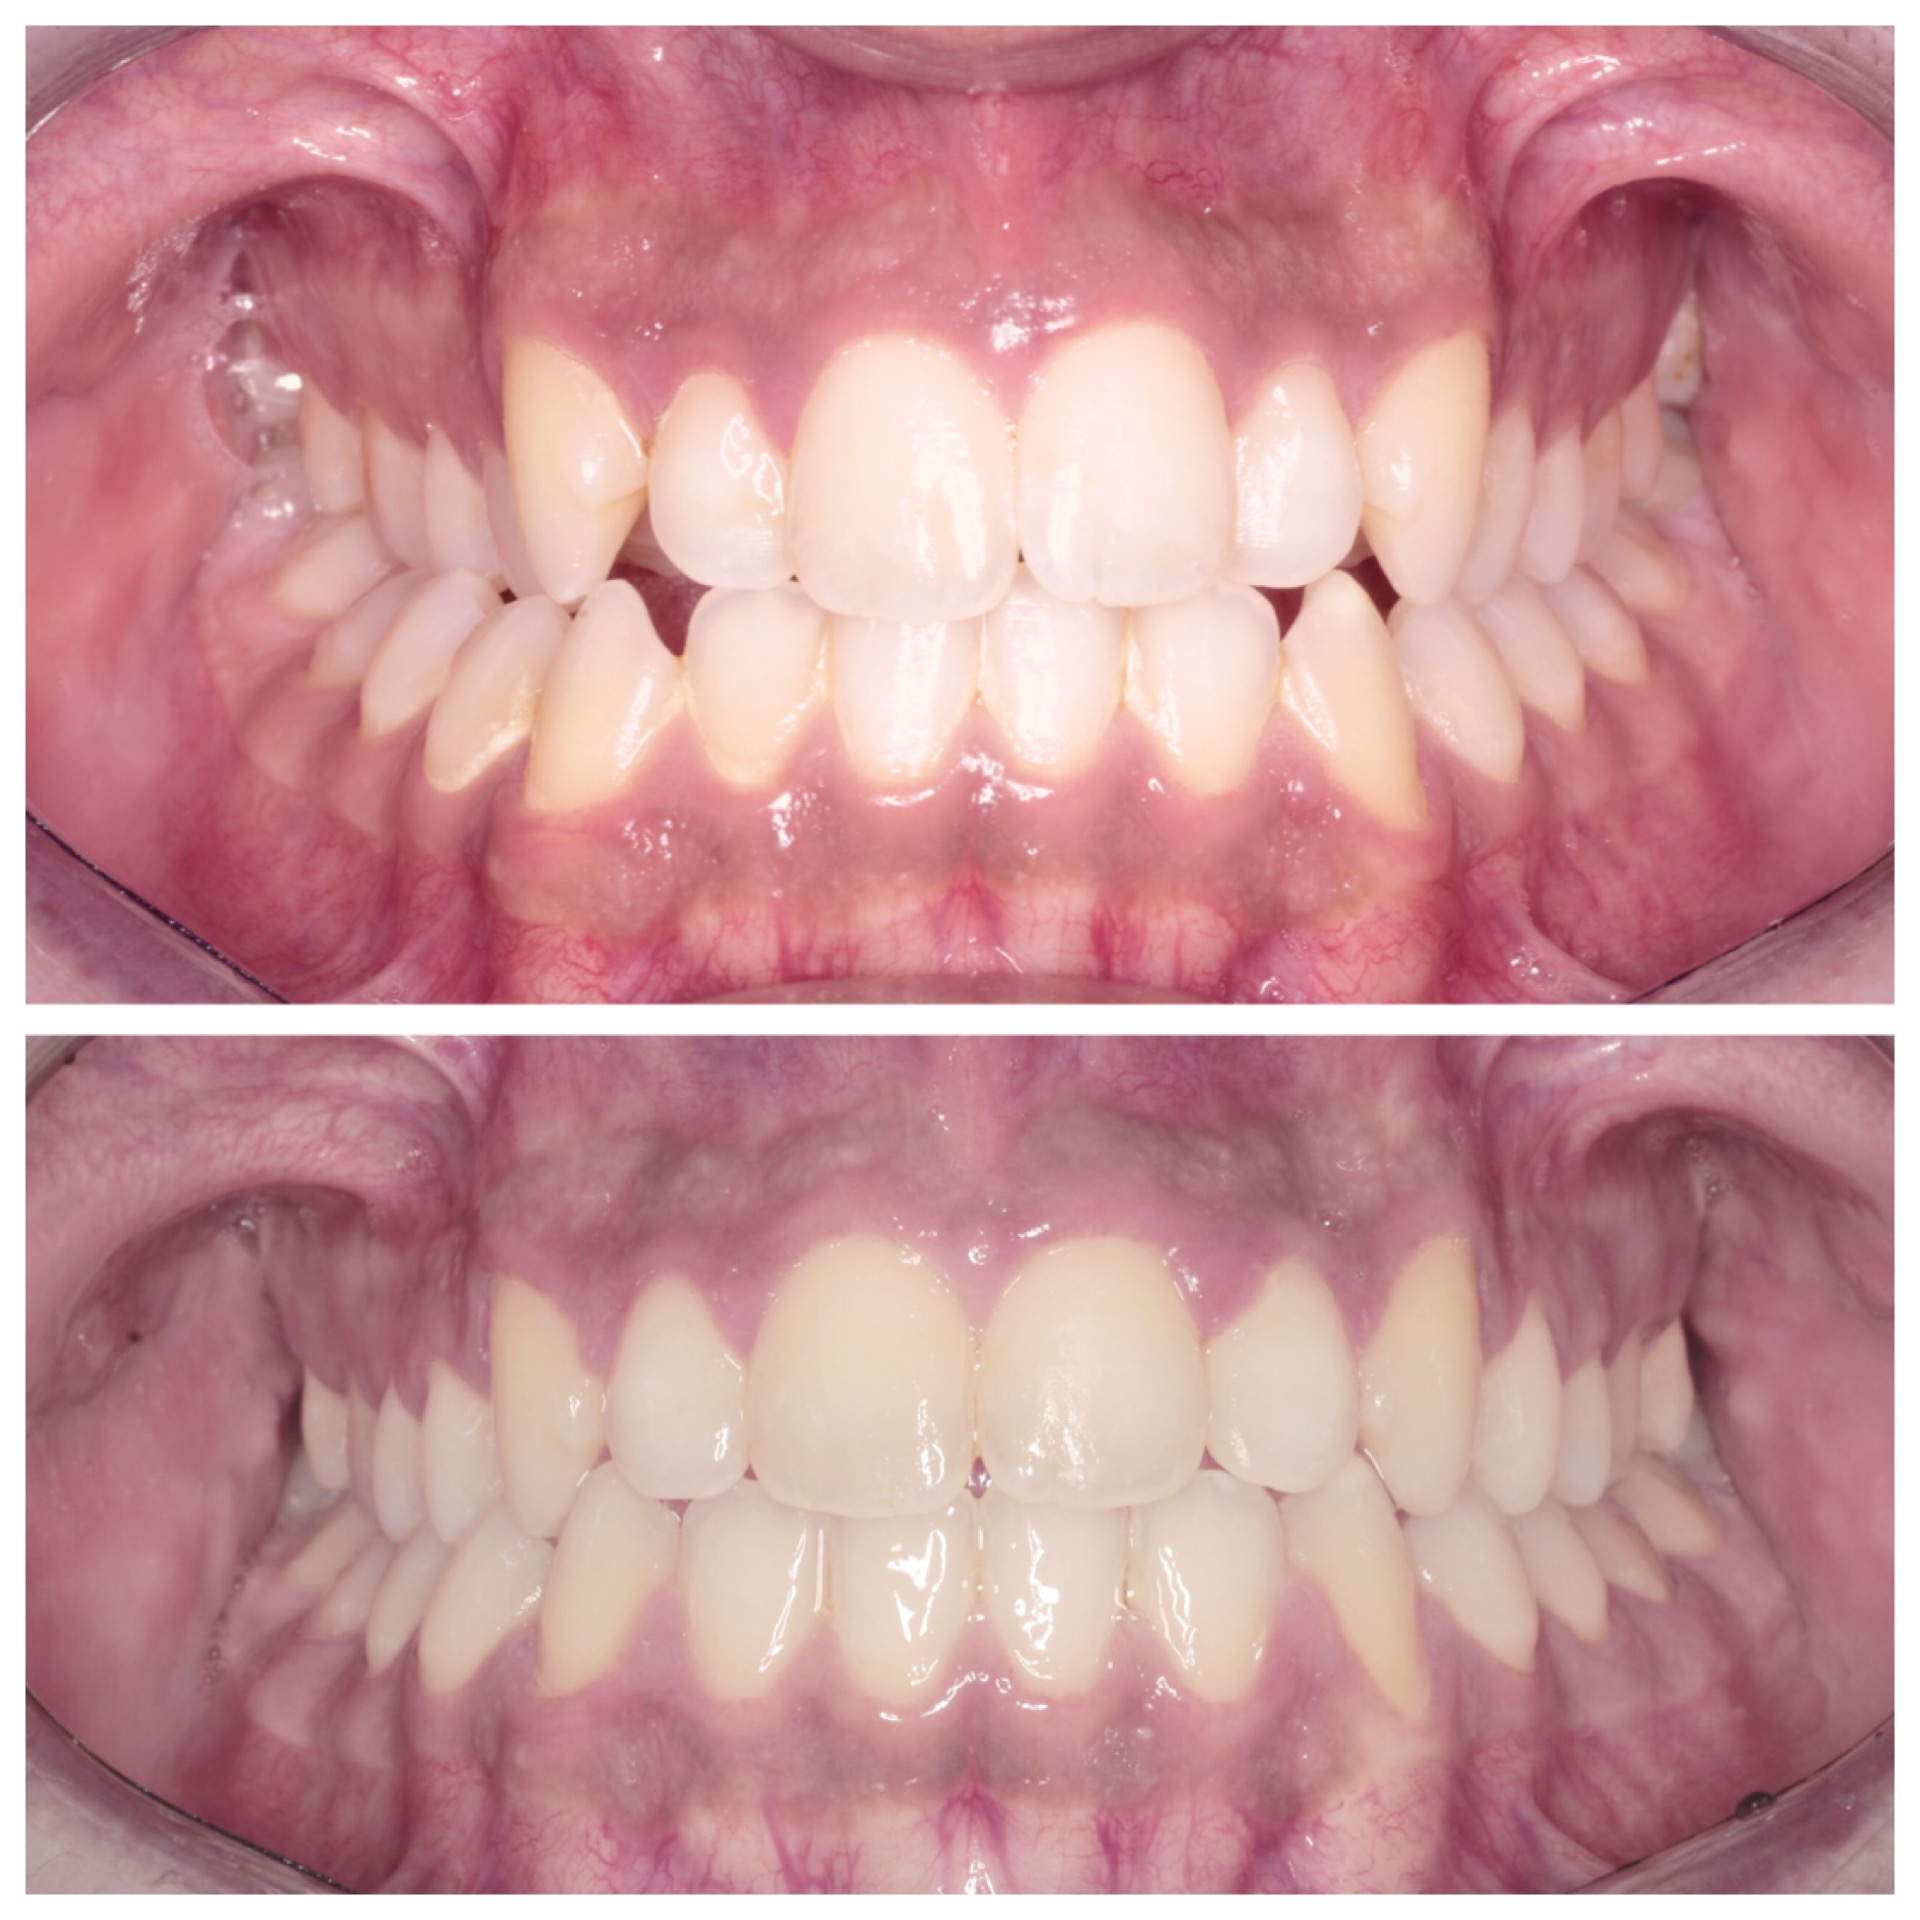

Con l’ortodonzia invisibile è possibile migliorare la propria immagine senza gli svantaggi di brackets e fili tradizionali ma con la stessa efficacia ed efficienza dell’ortodonzia convenzionale.

Mediante una serie di allineatori trasparenti e rimovibili, l’ortodonzia invisibile sposta i denti nel loro corretto allineamento settimana per settimana e, molto spesso, in meno tempo rispetto ai sistemi tradizionali.